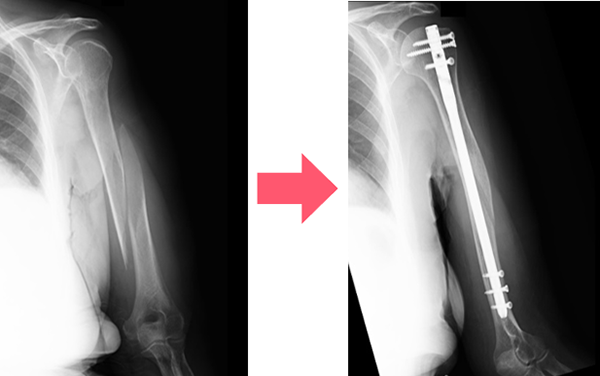

2. 手術治療

プレート固定や髄内釘(芯棒を入れる)固定などの手術療法があります。 どのような手術方法が良いかは骨折の場所や状態などを見て判断します。 粉砕骨折や軟部組織の損傷が激しい開放性骨折など、様々な理由ですぐにプレート固定や髄内釘固定手術が行えず、本番の手術までに待機期間を要する場合は、骨折部の上下に経皮的に骨にピンを刺入して体外でロッドを用いて連結させて骨折部を安定化させる創外固定という手術を応急的に行う場合もあります。手術は全身麻酔で行われることが多く入院が必要になります。

髄内釘固定